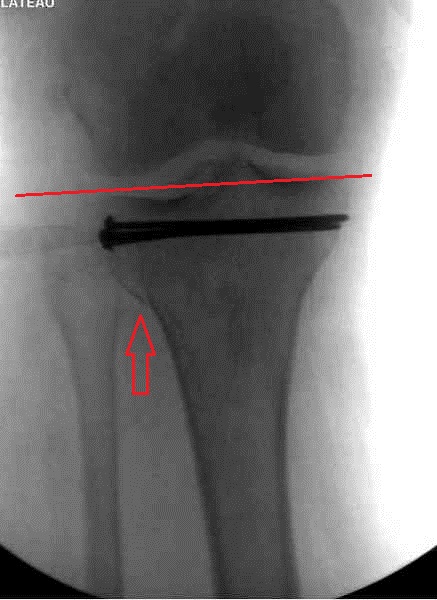

На представленном после операционном снимке нет репозиции на что указывает

низкое положение тибиального плато и перекрытие кортикальных пластинок в

метафизарной части - указано стрелкой. Обычно чрескожную фиксацию я применяю